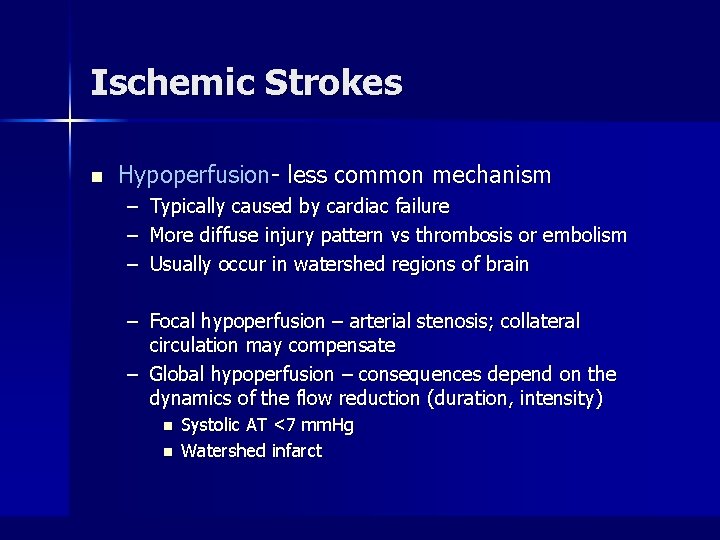

Ischemic Strokes n Hypoperfusion- less common mechanism – Typically caused by cardiac failure – More diffuse injury pattern vs thrombosis or embolism – Usually occur in watershed regions of brain – Focal hypoperfusion – arterial stenosis; collateral circulation may compensate – Global hypoperfusion – consequences depend on the dynamics of the flow reduction (duration, intensity) n n Systolic AT <7 mm. Hg Watershed infarct